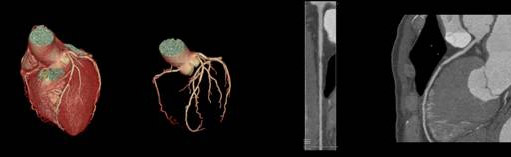

輪切りにする厚みは、最小0.625mmと細かい(薄い)画像が得られます。

これをコンピュータにより重ね合わせて、下記縦切り画像や3D画像を作成し診断に貢献させます。

当院では3台の64列CT装置を設置し検査を行っています。CT検査における被ばく低減と画質向上を目的とし、3台ともすべてに逐次近似法を応用した画像再構成法を導入しています。これにより従来と同程度の画像であれば従来のX線量の半分以下での画像化を、従来と同じX線量であればさらに高画質にすることが可能となりました。また、2022年には3次元画像解析システムSYNAPSE VINCENT(富士フィルム社製)を導入し、様々な診療科のニーズに対応しております。

当院での最高機種にあたるCTは、人体を透過したX線を検出する部分に新素材を採用し、これにより高精細な画像情報を提供するとともに、患者さんの被ばく低減も実現した装置です。アーチファクトやノイズも軽減され、細かい部分がはっきりと見えることにより内耳周辺の細かい骨の構造や血管情報、心臓では特にステント内腔の評価に優れています。また1つの管球で、2つの管電圧を高速で切り替えることにより、2つのエネルギーでの撮影が可能です。これにより画像コントラストの増強や金属によるアーチファクトの低減、骨、石灰化の分離により血管内狭窄の評価が期待されます。